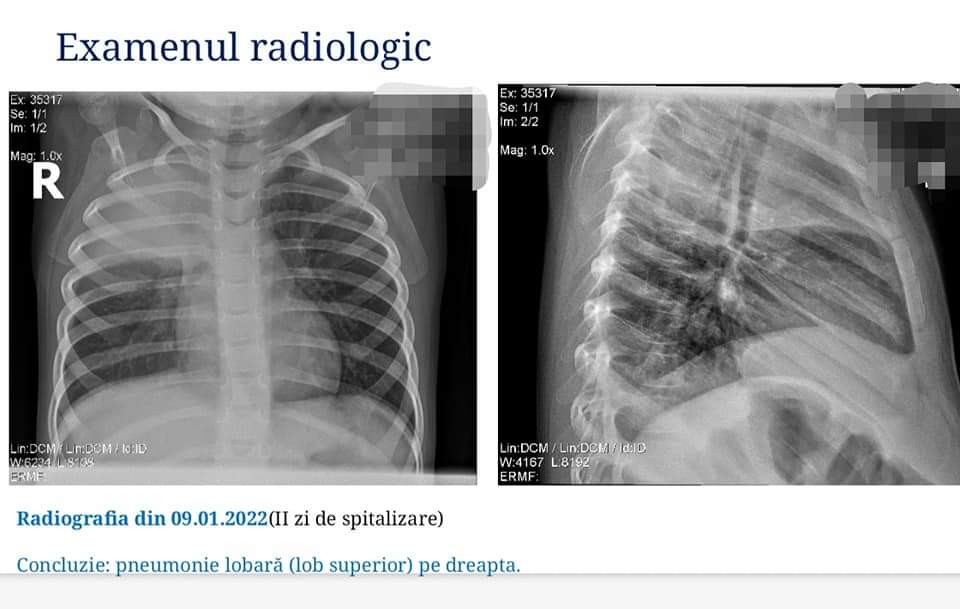

Cazul clinic relevant, asistat reușit în cadrul instituției în ianuarie 2022, a completat în mod deosebit informația prezentată. Doamna Neamțu Liuba, vicedirector medical, care a coordonat studiul de caz a prezentat evoluția procesului consultativ diagnostic al unui pacient în vârstă de 32 luni, cu diagnosticul de Pneumonie franc - lobară, în care ecografia pulmonară a permis identificarea pleureziei exudative și dinamica nefavorabilă a procesului pe fondal de tratament aplicat, influențând argumentat modificarea conduitei clinice.